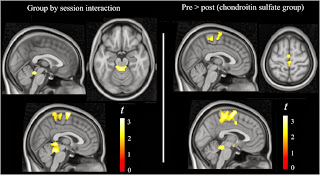

Los pacientes artrósicos que

recibieron condroitín sulfato experimentaron una mayor reducción de la

activación cerebral en respuesta al dolor provocado por la presión en la

rótula en diversas regiones cerebrales (p<0 .05="" i="">Es importante remarcar

que el efecto del condroitín sulfato se ha manifestado en la 0>

sustancia gris periacueductal y en las áreas motora y somatosensoriales de

la corteza cerebral, que son elementos esenciales en la fisiología de la

respuesta al dolor”,

**Se adjunta imagen de resonancia magnética

funcional perteneciente al ensayo clínico, en la que se muestra la reducción de

la activación cerebral en respuesta al dolor